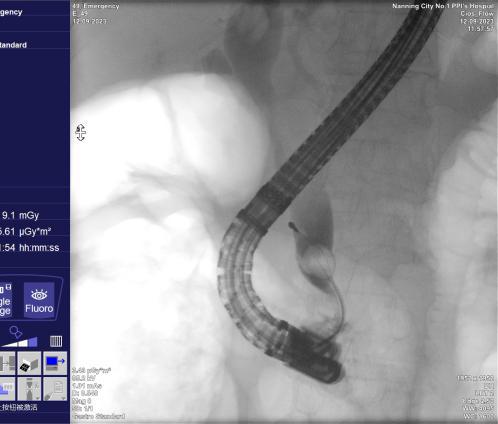

四、内镜下逆行胰胆管造影术(ERCP)

是指将十二指肠镜插至十二指肠降部,找到十二指肠乳头,由活检管道内插入造影导管至乳头开口部,注入造影剂后x线摄片,以显示胰胆管的技术。由于ERCP不用开刀,创伤小,手术时间短,并发症较外科手术少,住院时间也大大缩短,深受患者欢迎。适应于:1. 胆道梗阻引起的黄疸;2. 胰腺或胆道疾患(如结石、肿瘤、硬化性胆管炎等);

胆总管结石造影所见 网篮取出结石

十二指肠乳头癌 十二指肠乳头插管

胆管金属支架置入过程 金属支架置入术后